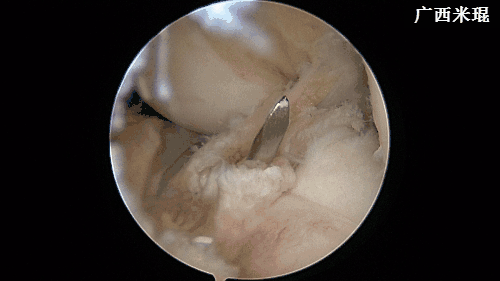

(十七)维合切口

关节镜下检查重建的ACL走向以及张力,屈伸膝关节时观察重建的ACL是否与髁间窝撞击,确认良好后缝合各切口。此过程 一般需要2分钟。